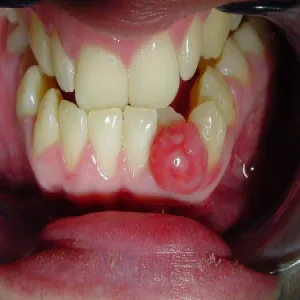

Nadziąślak

Nadziąślak, epulis